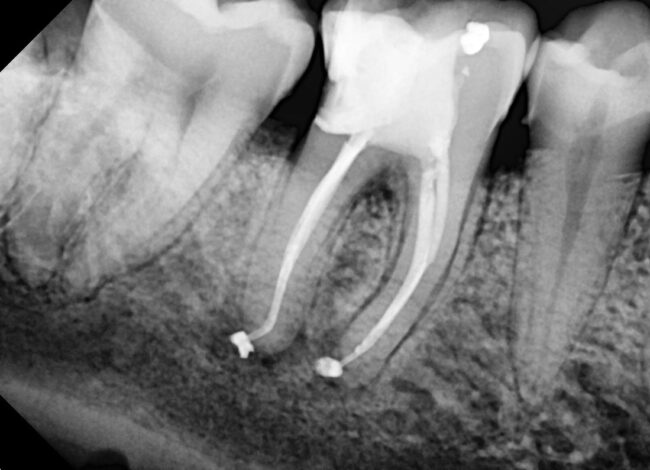

Biopulpectomía en pulpitis irreversible utilizando BlueShaper®, Z-Glider, Fast Pack y Fast Fill

Caso de pulpitis irreversible tratada con los sistemas de instrumentación BlueShaper® y limas Z-Glider ambas de Zarc por el doctor José Conde en su clínica de endodoncia exclusiva, Clínica Conde País.